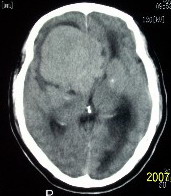

f    29岁   头闷  头晕1月余

肿瘤累及颅底前颅窝,部分层面见散在钙化,中心坏死。支持:脑膜瘤!

这么大,鞍上压迫那么厉害,梗阻也比较重没有视力及其他症状吗?从肿瘤本身表现看,支持考虑颅底脑膜瘤

肿瘤长入侧脑室,侧脑室明显扩大, 病灶边界清楚,其内可见低密度坏死区,中枢神经细胞瘤?室管膜瘤?

镰旁高密度灶,中间低密度坏死区,周围水肿较轻,支持脑膜瘤诊断,建议结合增强扫描。

右额叶底部巨大等低混杂密度肿块,边界清楚,周围水肿轻度,明显占位效应。蝶鞍扩大,部分骨质破坏。

考虑脑膜瘤,建议增强扫描进一步检查。

蝶鞍受压吸收,可以排除室管膜瘤。肿瘤最大层面不在蝶鞍可以排除垂体瘤。支持脑膜瘤